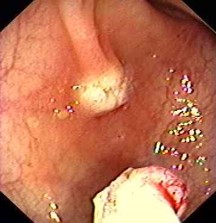

Vorsorge Darmspiegelung / diagnostische Darmspiegelung

Präventive Koloskopie (Vorsorge Darmspiegelung)

Darmpolypentfernung / ambulante Polypektomien

Diagnostische Koloskopie zur Abklärung abdomineller Beschwerden, ggf. mit Probeentnahmen (z.B. bei Verdacht auf chronisch-entzündl. Darmerkrankung)

Endoskopische Tumornachsorge

Magenspiegelung (Ösophago-Gastro-Duodenoskopie)

Zur Abklärung von Oberbauchbeschwerden, Schluckbeschwerden, Sodbrennen etc.

Testung auf Helicobacter pylorii

Endoskopische Entfernung von PEG Sonden (MagenSonden)